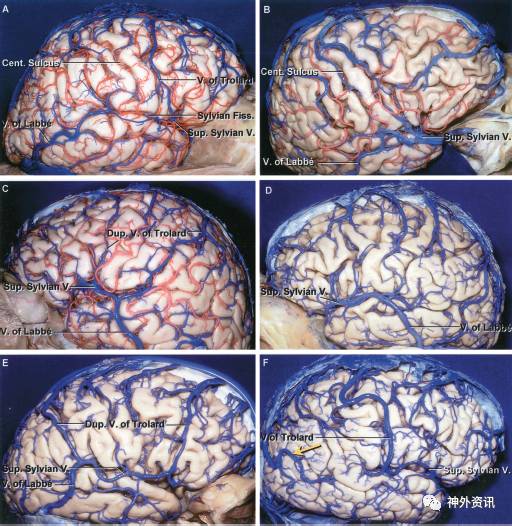

图4.11. 不同大脑半球静脉引流的模式。A. 右侧侧面观。引流大脑半球的静脉直接汇入上矢状窦和横窦。侧裂浅静脉(superficial sylvian vein)很小,一支很小的Trolard静脉将上矢状窦和侧裂静脉相连。B. 右侧大脑半球(另一标本)。侧裂浅静脉很大,在侧裂浅静脉和引流至上矢状窦的静脉之间只有很小的吻合支,而在侧裂浅静脉和Labbe静脉之间存在连接。此类病例,当采用翼点入路打开侧裂时,整个大脑半球的静脉引流模式不甚清楚。牺牲诸如图A中的侧裂浅静脉很可能不会影响到大脑半球的静脉引流,而牺牲诸如图B所示的较大的侧裂浅静脉,很可能导致汇集额侧和颞侧侧裂区域的静脉回流障碍;C. 左侧大脑半球。侧裂浅静脉和Labbe静脉之间存在主要的连接。除此之外,较小的双干Trolard静脉将上矢状窦与侧裂静脉相连。Trolard静脉的后支在临近Labbe静脉的结合部与侧裂浅静脉相连接。D. 左侧大脑半球。在侧裂区静脉和上矢状窦之间无明显的吻合支,但是,在侧裂浅静脉和Labbe静脉之间有一支很大的吻合支。E. 右侧大脑半球。双干Trolard静脉将侧裂浅静脉与上矢状窦相连接,一支跨过额叶,一支跨过顶叶。同时,侧裂浅静脉与Labbe静脉之间也存在很大的吻合支。F. 右侧大脑半球。位于中央沟区域的单支Trolard静脉将侧裂浅静脉与上矢状窦相连。未见发育良好的Labbe静脉,但在顶后和颞叶区域可见一支较大的静脉(黄色箭头)引流至上矢状窦。

Cent. = central (中央的);Dup. = duplicate (双干的); Fiss. = Fissue (裂);Sup. = superior (上) (注:原文此处有误,结合图释,此处Sup.应为superficial (表浅的));V. = vein (静脉)

(Rhoton et al. Neurosurgery. 2002, 51(suppl 1):173. 中文版见:刘庆良等. Rhoton颅脑解剖及手术入路,p201.)